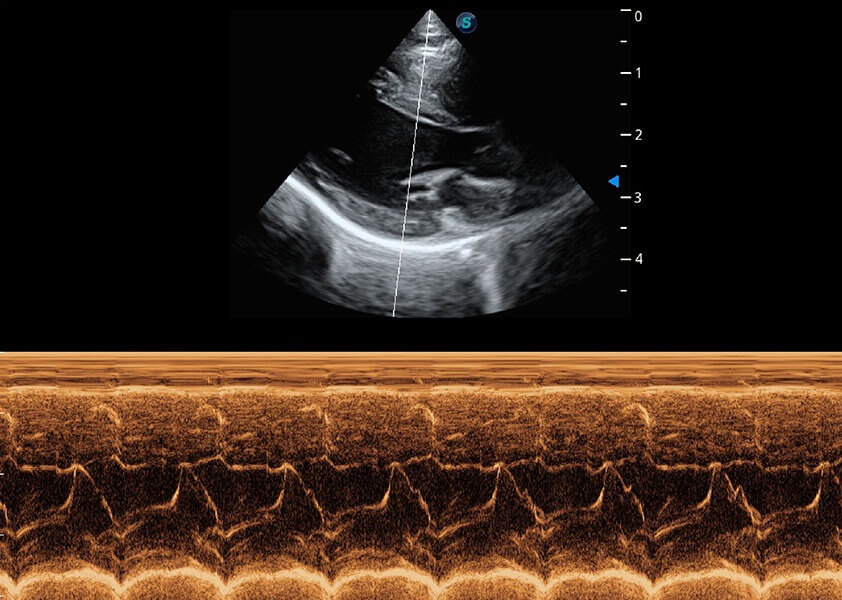

ProPet 60 作为一款高端台式动物超声设备,为动物医生的日常诊断提供了一系列贴合动物临床需求、解决临床实际问题的高级成像功能。凭借全系列高清探头,满足医生对腹部、心脏、生殖、浅表、肌骨等成像的所有需求,切实帮助您提升检查效率,提高诊断信心。

兽用彩色多普勒超声诊断系统